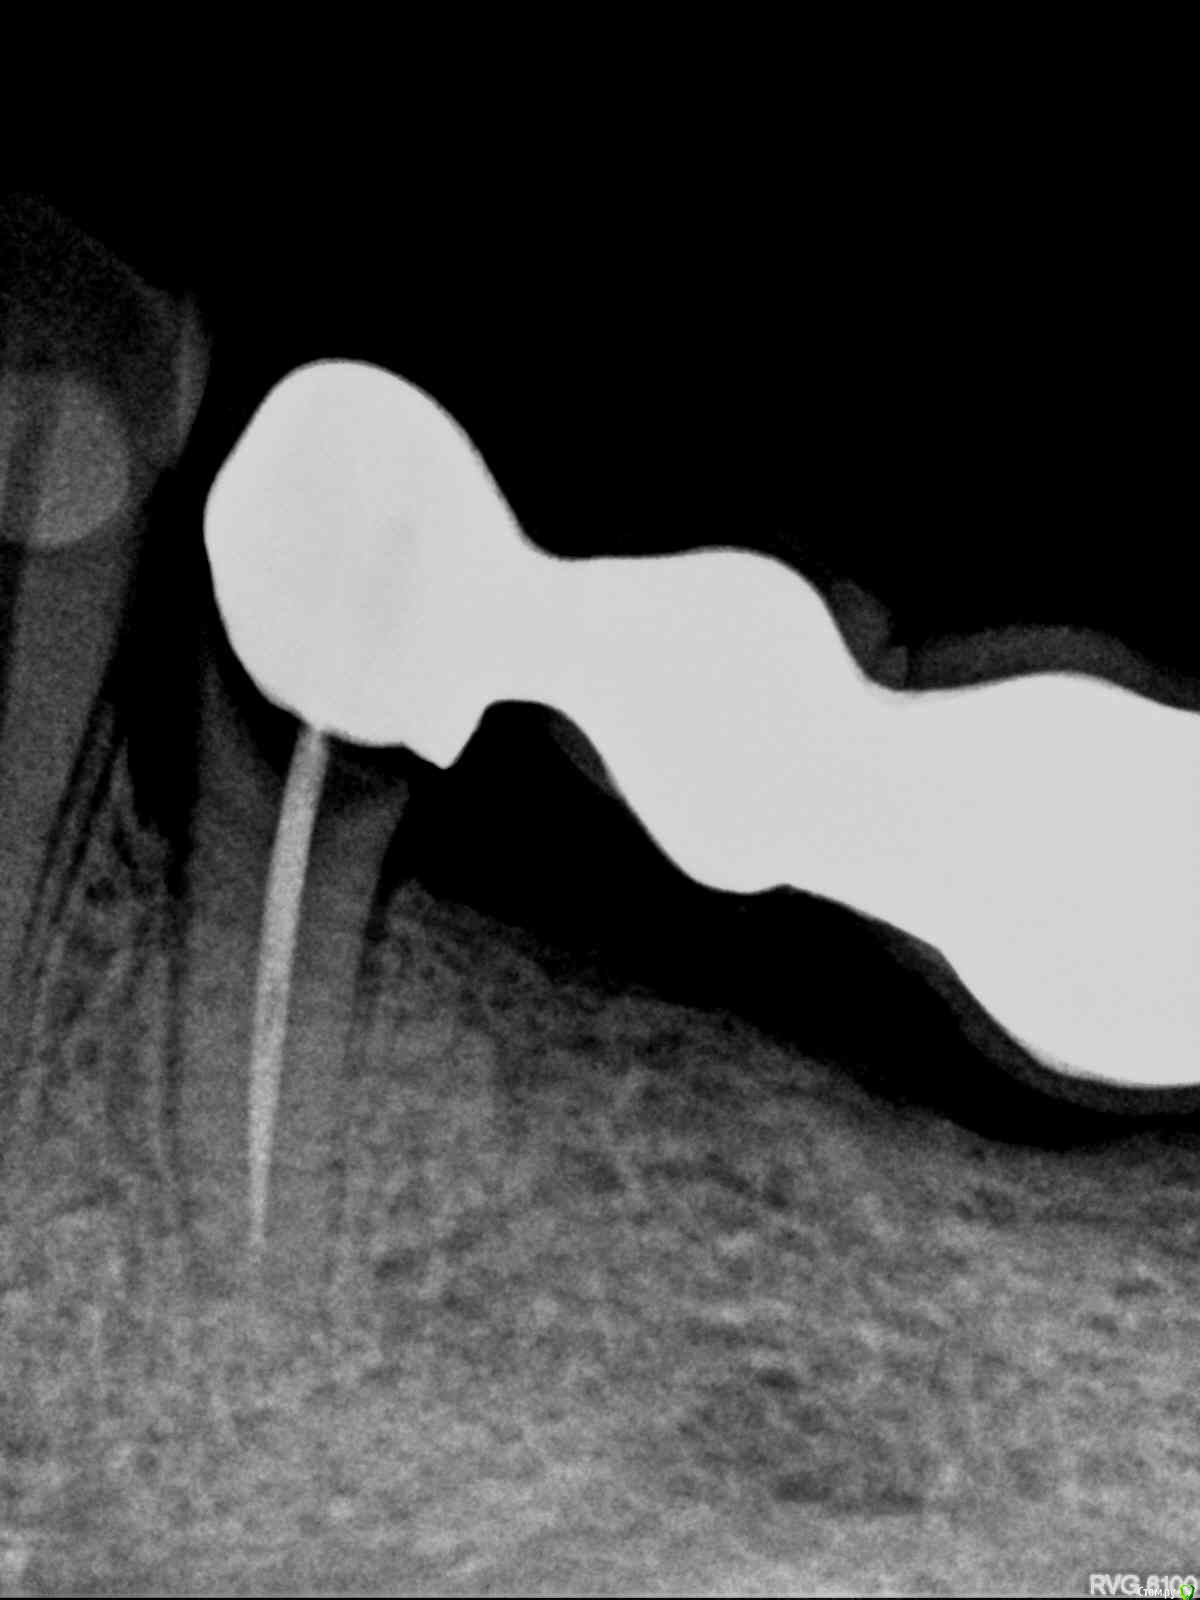

lazzal Опубликовано 29 октября, 2015 Поделиться Опубликовано 29 октября, 2015 (изменено) Уважаемые ортопеды, дайте пожалуйста совет и свои рекомендации. в 2012 г была установлена конструкция на передние верхние зубы из безметалловой керамики. 2 мини моста резец-клык справа и слева. устанавливались на свои абсолютно здоровые зубы, предварительно депульпированные, так сделать предложил врач, чтоб была типа "голливудская улыбка". у меня от природы отсутствовали двойки с обоих сторон, правда зазор был не большой, но все равно смотрелось не очень, клыки сразу бросались в глаза. так вот, врач мне сказал, что конструкция прослужит 20 лет, а у меня через 2,5 года начались проблемы. начали чернеть кромки вдоль конструкции с внутренней стороны. терапевт диагностировал кариес. ортопед сказал снимать не надо, можно их изнутри немного сточить, пролечить кариес и запломбировать. так и сделала. но пломбы теперь вылетают каждые 3-4 месяца. врач который лечит, сделал снимки и сказал, что там с правой стороны между резцом и клыком гниет корень и надо конструкцию снимать, а то потеряем корень. мой ортопед же говорит, что все нормально - пусть стоят, надо лучше пломбировать. снимать я сама не хочу конечно. но корень дороже. кто из них прав и что мне делать? еще сложность в том, что конструкция похоже крепится на какой-то супер клей и просто так ее сбить или спилить не получится (проговорился мой ортопед). я не представляю как это все может выглядеть, стешут по самые десны и сделают вкладки? очень бы этого не хотелось, т.к. хотелось бы этот вариант оставить про запас, т.к. потом, если что случись - олько имплантация и то, если это будет возможно. Посмотрите снимки и подскажите, что можно сделать им почему такой короткий срок службы? как смог развиться кариес? Так же прилагаю и панорамный снимок, возможно вы увидите и укажете мне на еще какие-то проблемы с зубами или деснами, на которые стоит обратить внимание. С уважением и благодарностью, я. Изменено 29 октября, 2015 пользователем lazzal Ссылка на комментарий

lazzal Опубликовано 30 октября, 2015 Автор Поделиться Опубликовано 30 октября, 2015 Посмотрите пожалуйста в каком состоянии зуб под коронкой, возможно ли его спасти? Ссылка на комментарий

Bier Опубликовано 30 октября, 2015 Поделиться Опубликовано 30 октября, 2015 В плачевном состоянии, его сохранение под вопросом 1 Ссылка на комментарий